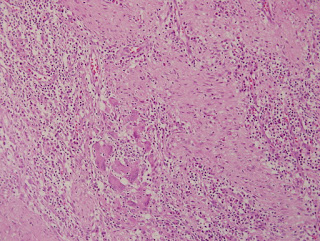

fig-3-histology-of-the-pancreatic-rest- February 24, 2020 320 × 241 fig-3-histology-of-the-pancreatic-rest-